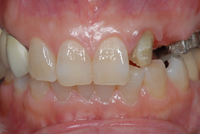

インプラント治療の症例(上顎)

治療前

上あごの歯がほとんどありません。普段は入れ歯を使っていますが、残った歯への負担も大きいようです。

治療中

歯のない部分にインプラントを埋入しました。

残っていた状態の悪い歯も抜歯をし、順次インプラントに置き換えます。

治療後

最終的に上あごには8本のインプラントを埋入しました。

前歯を近くから見ても天然の歯のような自然な仕上がりです。